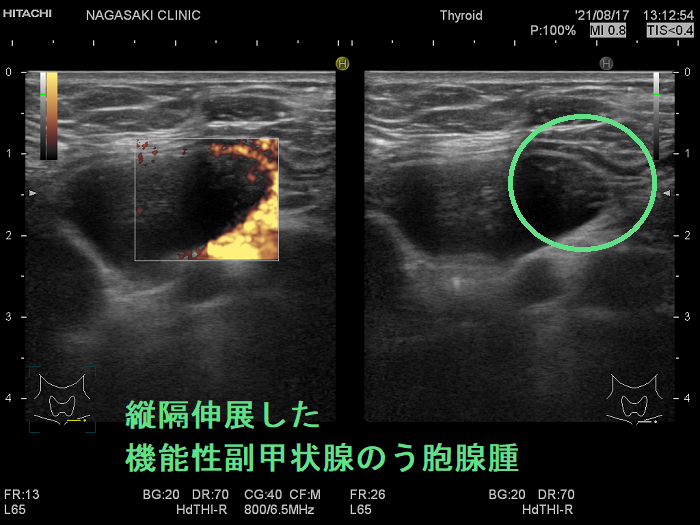

超音波(エコー)検査で見つからない副甲状腺は、

- 縦隔内

- 食道背側

- 喉頭背側

に存在する場合です。

造影CTで副甲状腺腫瘍の位置を再確認します。

原発性副甲状腺機能亢進症手術症例の2.6-6.8%は、定位置にない異所性副甲状腺腫です。縦隔などエコーが届かない場所にある異所性副甲状腺腫に、造影CT, 99m-Tc MIBI-SPECTは有用です。